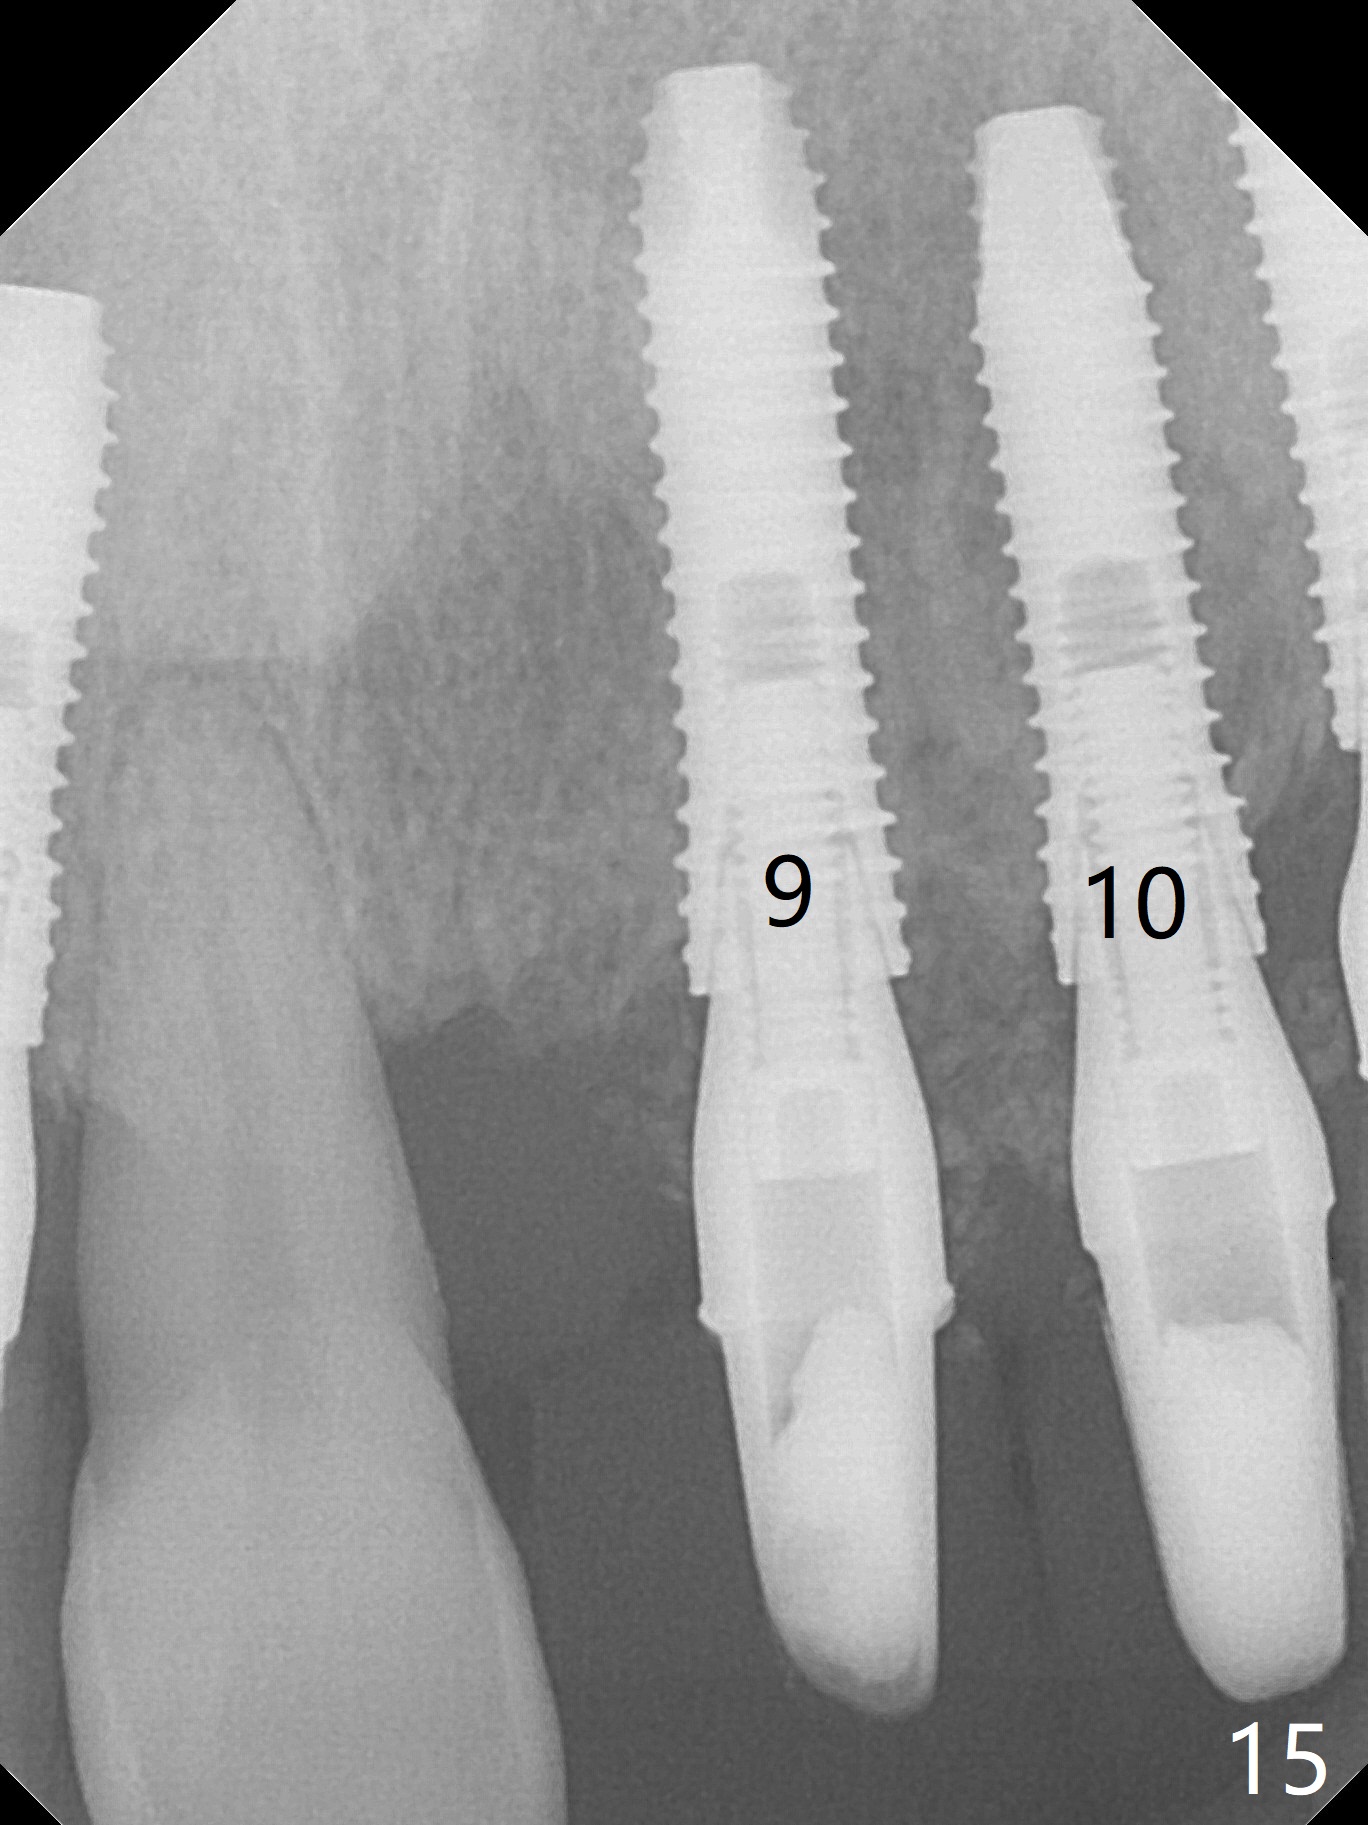

The dentition is poor except #6 and 8 (Fig.1). The gingiva is erythematous at #9-11 (Fig.2). The teeth #9 and 10 are extracted first; a 4x16 mm UF implant is placed at #9, while a 2 mm pilot drill is at the site of #10 (Fig.3). The implant at #9 is placed deeper with placement of 4.5x5.5(5) mm abutment; a 3.8x15 mm implant is placed at #10 initially (Fig.4). While the latter is placed deeper, a 4x16 mm implant is placed at #11 (Fig.5 after removal of #11-15 FPD (fixed partial denture)). In fact the trajectory at #11 is not difficult to be changed with 2 mm drill (Fig.6). After use of 3 mm drill, the implant is reinserted at #11 with ideal trajectory (Fig.7). After further seating of the implant at #11, graft is placed in the remaining sockets of #9-11 (Fig.8 *; later more graft is placed mesial to #11 implant (^)). Finally, a 4.5x7(5), 4.5x15° B (4) and 5.5x7(5) mm abutments are tightened and prepared (Fig.9) for splinted provisional at #9-10.

The patient returns 8 days postop, uncomfortable with overhang in the provisional (Fig.10 *). The sockets appear to be healing with loose bone graft (Fig.11) when the provisional is removed for trimming (Fig.12). Six (for #7,13) and seven (#9-11,15) months postop, the soft (Fig.13,17) and hard (Fig.14-16,18) tissues heal. It appears that the trajectory at #9,11 and 13 should be changed by using angled abutments (Fig.18,19 (panoramic X-ray taken 2 months earlier)) before provisional and final restoration.

In fact angled abutments are used at #11 and 13 (4.5x15 degree (5 mm)A) with a straight abutment at #15 (5.5x4(4) mm).